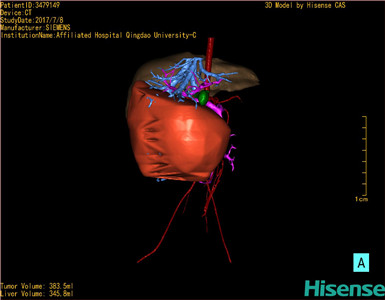

将0.625mm双源薄层CT资料的静脉期和动脉期Dicom格式文件导入海信CAS系统。

通过调节窗宽窗位调整CT序号,对肝实质,胆囊,下腔静脉,肿瘤,肝动脉、门静脉及肝静脉等进行三维重建;系统自动计算肝脏体积。

模拟手术操作,自动计算切除肿瘤体积。肝脏体积为345.8ml,肿瘤体积383.5ml,是肝脏体积的1.1倍,通过比对6-9月岁正常肝脏体积为257.75±51.05ml,通过术前模拟手术,精准判断切除后剩余肝脏体积能耐受,避免肝衰竭发生。

术前三维重建:

重建图片